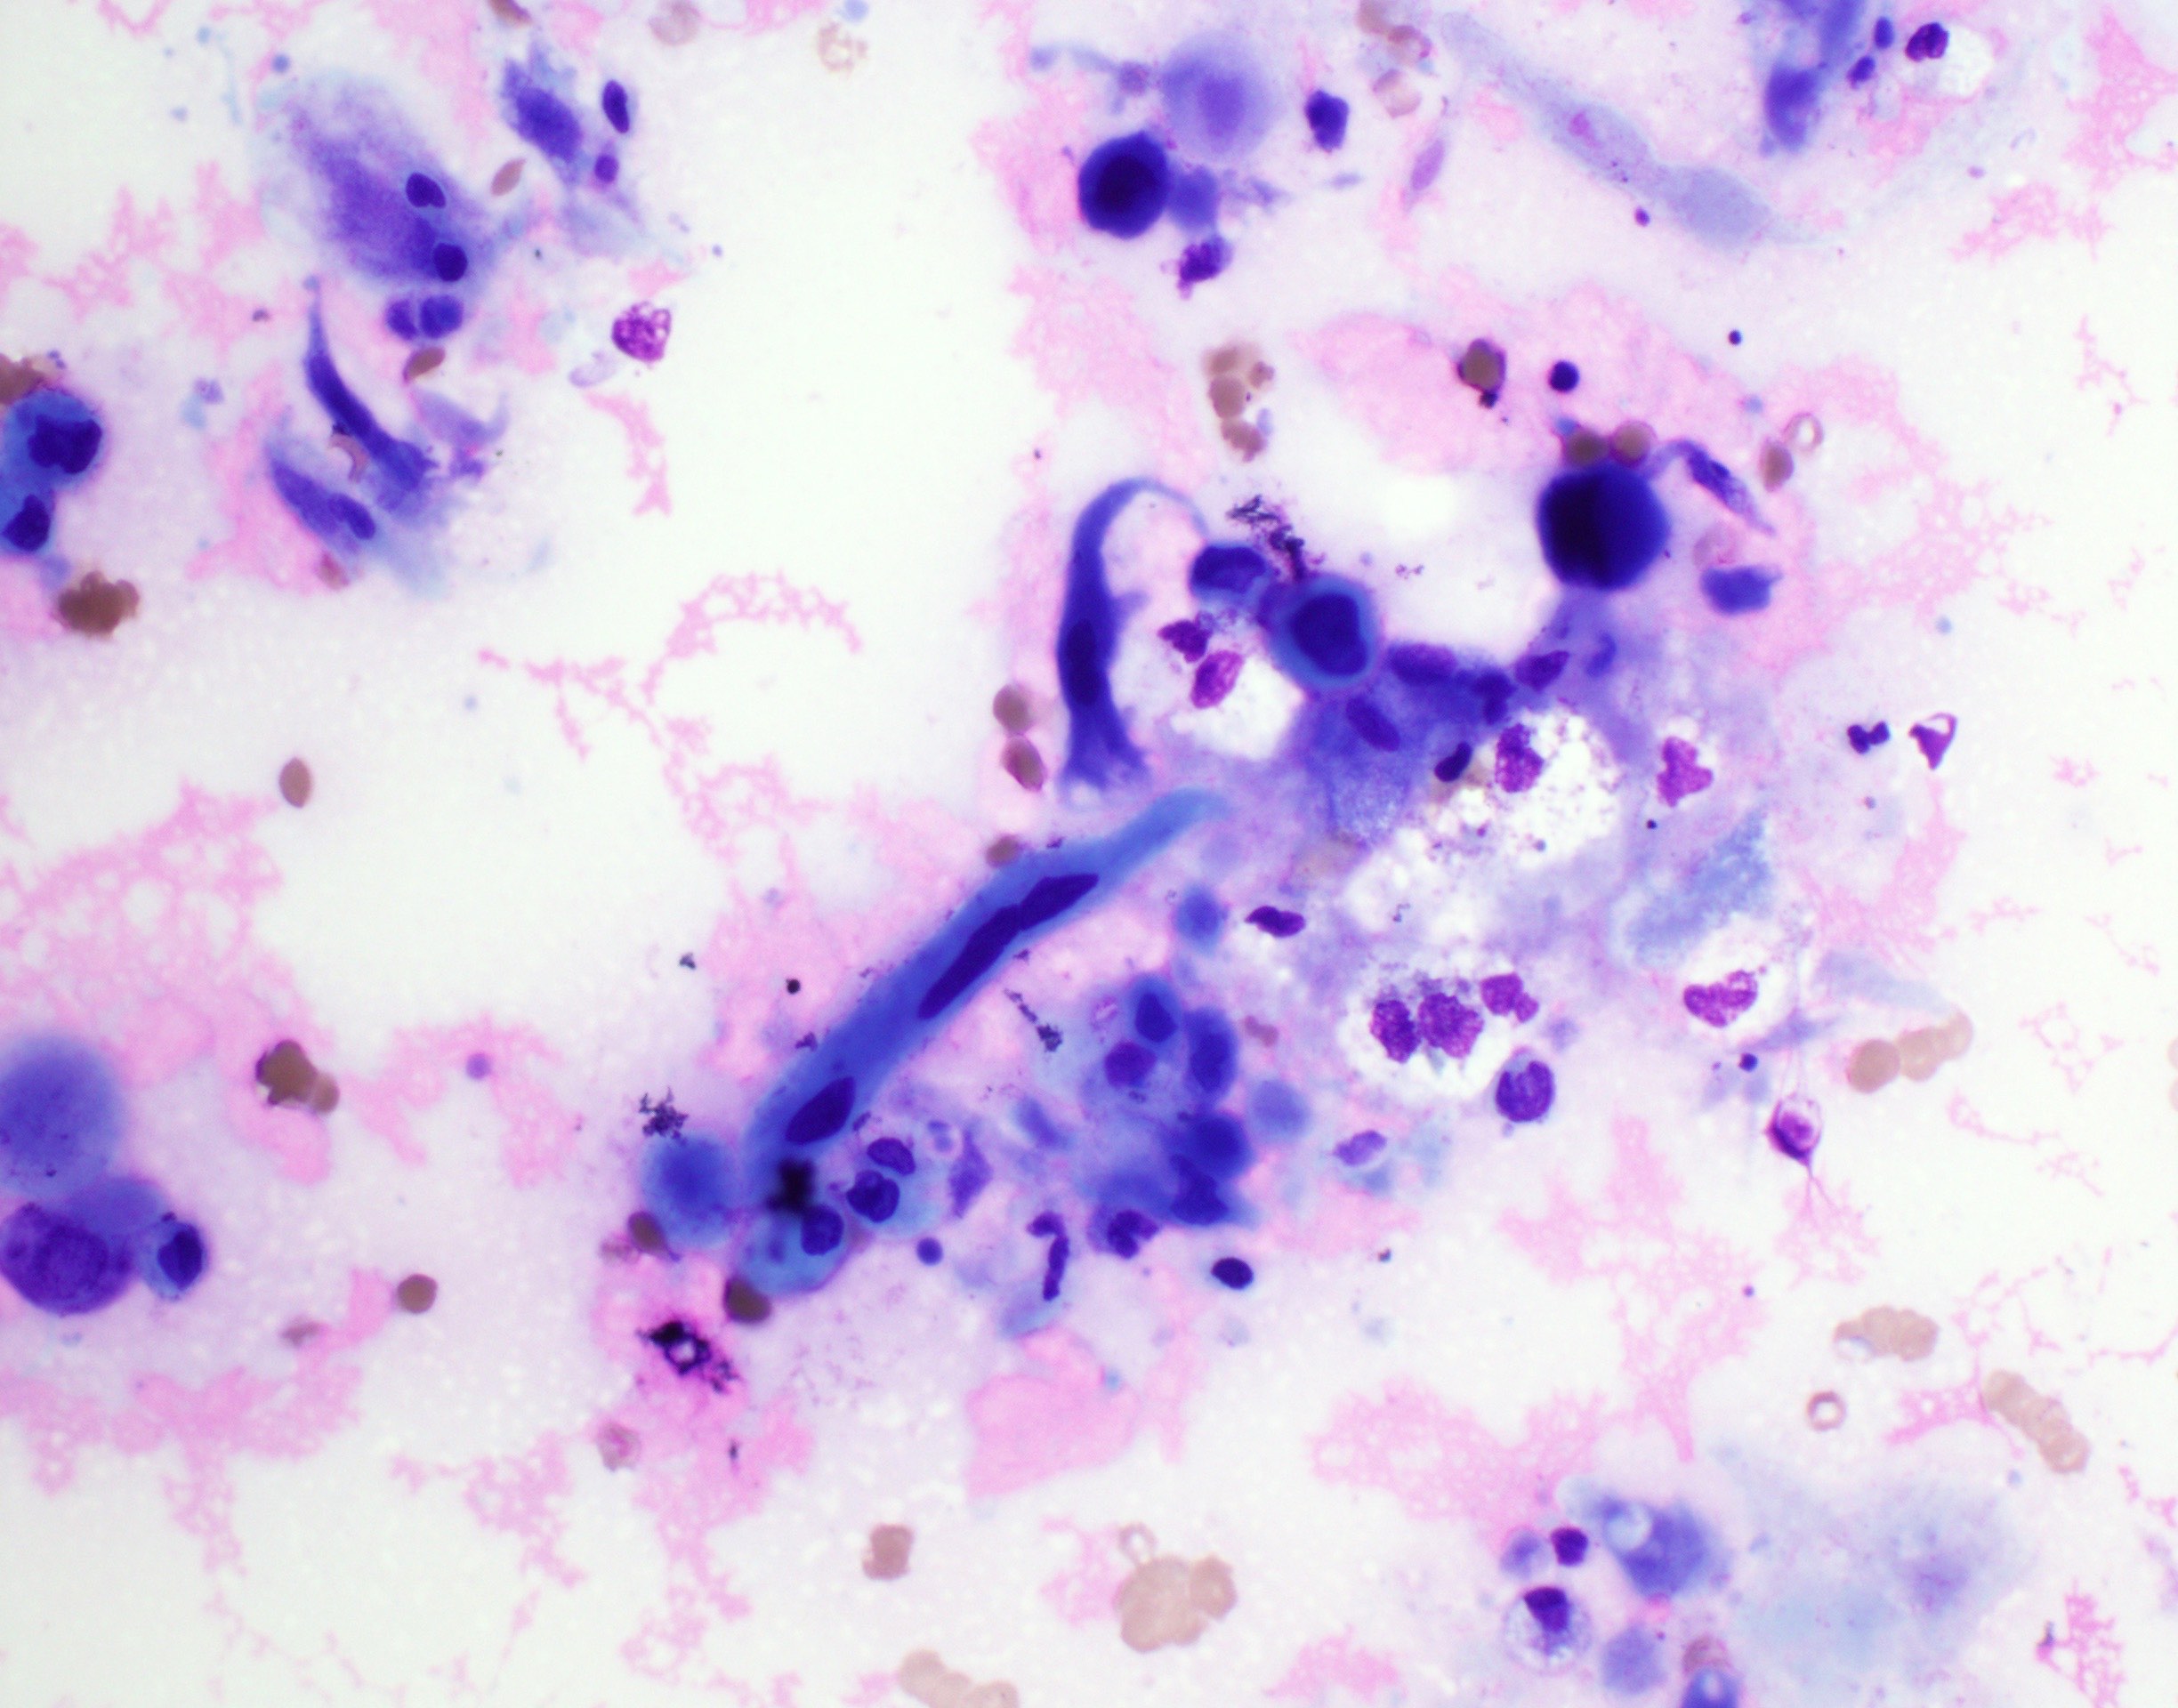

Cytology description

- Role of cytology only in investigation of regional or distant metastases

- Appearance depends on type and differentiation

- Conventional squamous cell carcinoma shows sheets and small clusters of large polygonal malignant cells with intercellular bridges and cytoplasmic or extracellular eosinophilic keratin

Cytology images